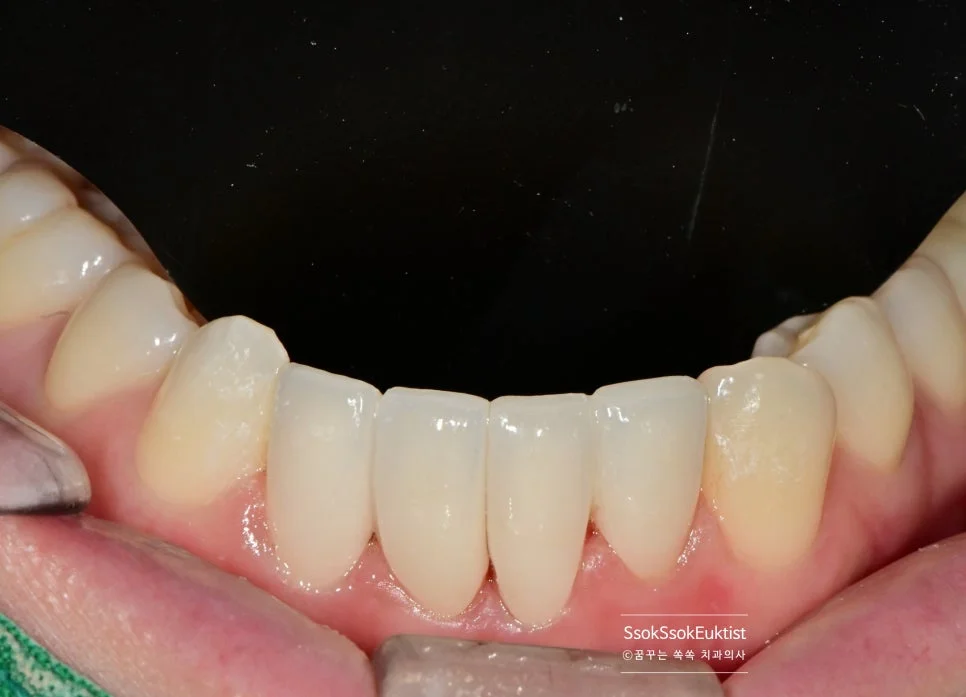

아래 앞니 4개 크라운 최종 결과 — 가지런하고 심미적인 치아

짜잔!

가지런하고 예쁜 치아인 것 같나요?^^

치아 뿌리의 위치와 모양은 정해져 있기 때문에 아래쪽으로 갈수록 살짝 어색한 느낌은 있지만 비교적 가지런하고 심미적인 크라운이 제작되었습니다.